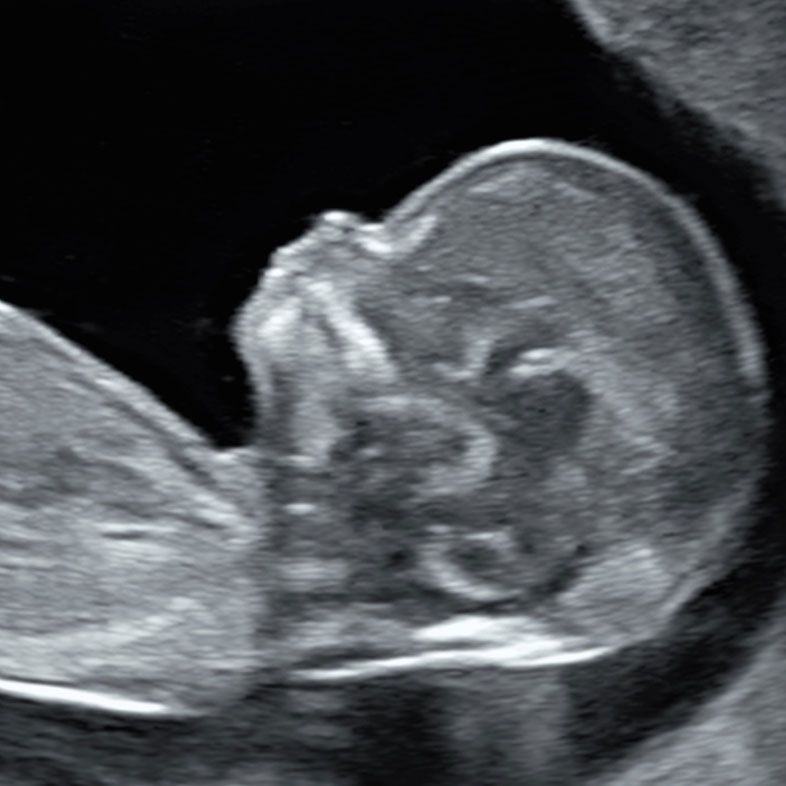

Anytime Reassurance at any stage of your pregnancy

Our Fetal Medicine experts are available for non-urgent reassurance scans as well as second opinion on a diagnosis you may have had elsewhere. Please note, that we provide an advanced diagnostic services, not a counselling regarding management of fetal or pregnancy abnormalities.

We are fully committed to providing the best possible diagnostic imaging and doing everything we can to exclude any fetal anomalies or conditions. The structures we examine will primarily depend on the gestational age and other circumstances. However, every scan will include an examination of the fetal brain and heart.